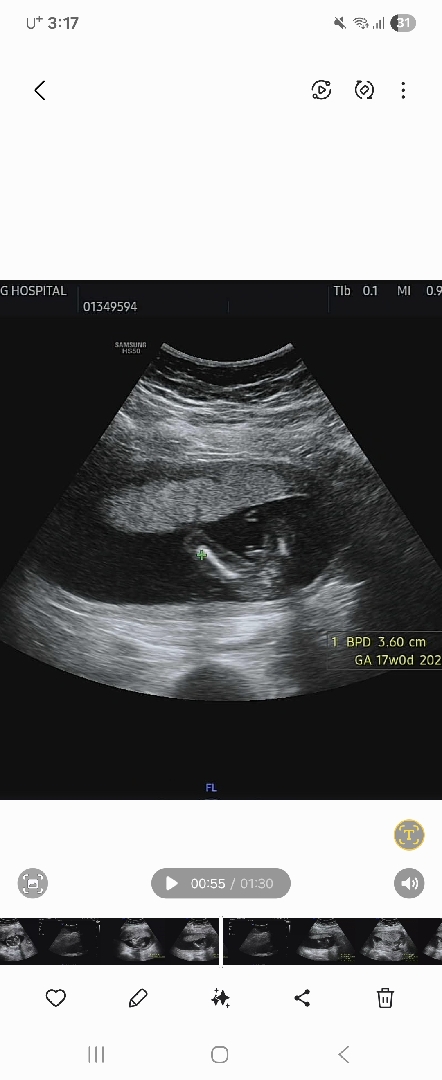

각도좀봐주세용 고수님들^^♡

선생님이 탯줄일수도 있고아닐수있다던데 고수님들봐주세요♡